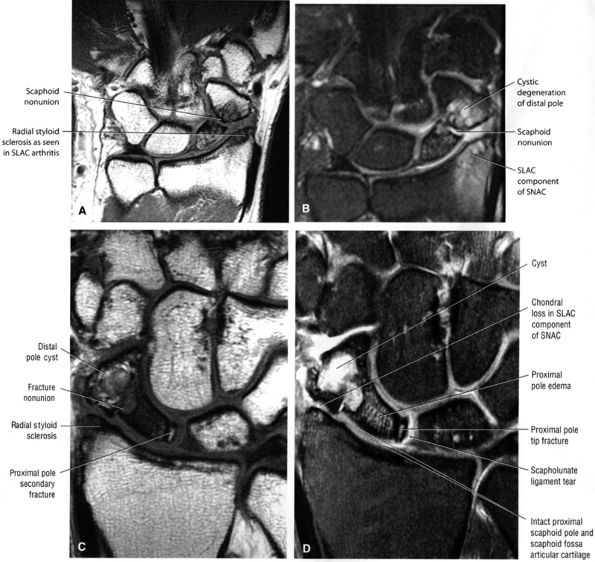

|